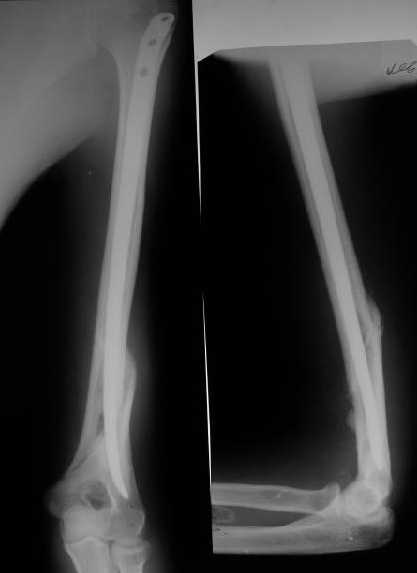

Огромное спасибо всем принимающим участие в дискуссии. Вначале отвечу на поступавшие персональные вопросы: 1. обстоятельства травмы - соревнования по армрестлингу (от себя замечу, что у военных нередкая травма в последнее время! На мой взгляд это связано с вовлечением в это дело неподготовленных людей - командирам нравится, т.к. в плане реквизита намного легче организовать чем традиционное перетягивание каната...). 2. в отношении провокационной составляющей - она присутствует, но лишь в той степени в какой любое инициирование дискуссии несет в себе элемент провокации... 3. про актуальность консервативного лечения - мне кажется это актуально всегда и при любой локализации если врач владеет методом, например, часто наблюдал великолепные функциональные результаты консервативного лечения переломо-вывихов голеностопных суставов... Тут только надо помнить, что "консервативное" это тоже лечение (контроль, тяги, перекладывание повязок), а не просто накладываем гипс и через энное время говорим, что не получилось и берем на операцию.

Теперь непосредственно по больному. Лечим функциональной повязкой, добились вот чего (приложение). Будем признательны за дальнейший комментарий - мое мнение, что можно продолжить без операции.